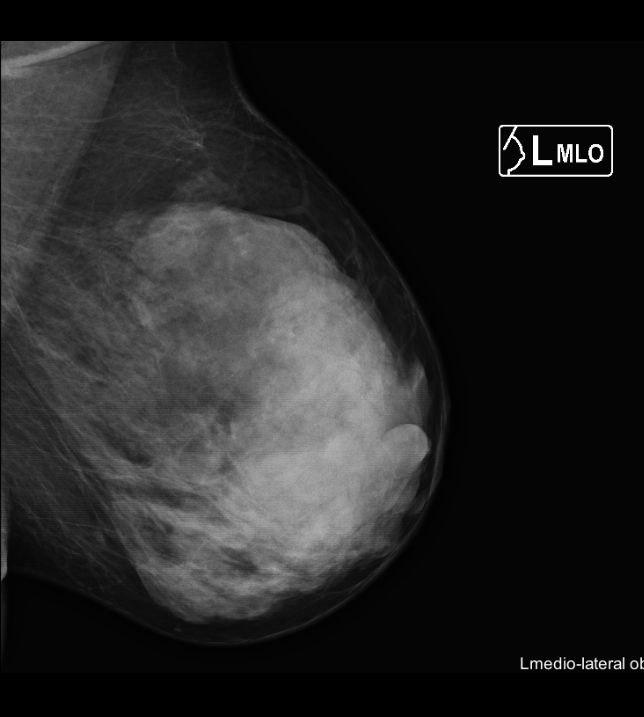

Инволютивные изменения в молочной железе